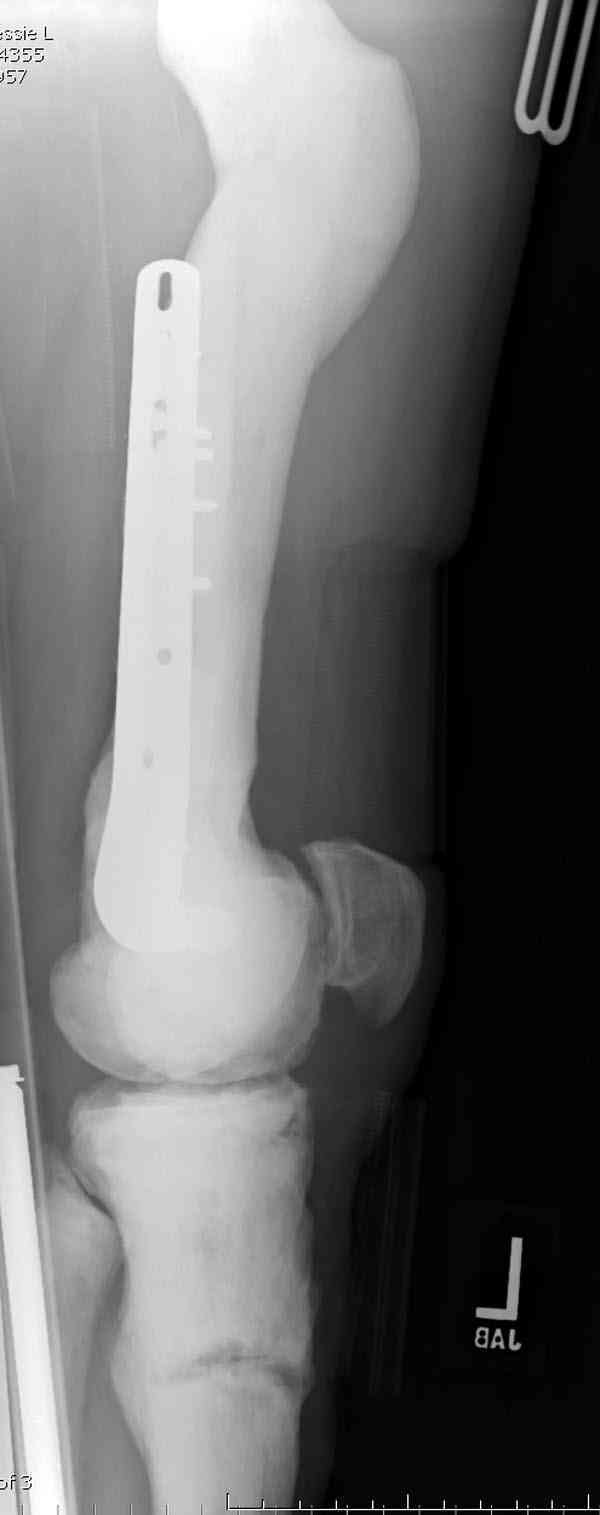

⌠При лечении переломов у больных с остеопетрозом (в прошлом году был

случай) необходимо быть готовым к длительным операциям из-за трудности

обработки традиционными методами ⌠мраморной■ кости, иметь в наличие

достаточное количество свежих острых инстументов и персонала при

необходимости замены (были случаи отстрочки операции на следующий день

из-за физической усталости персонала), и надо избежать особо

трудоемких операции как интрамедулярное сверление■.

Не являюсь специалистом по костной патологии, но мне кажется, на

ренгенограмме множественные мета-диафизарные образования напоминяющее

змееподобных извилистых линии и периостеальные ламинирование очень

напоминяет картину остеонекроза (инфаркта) костей, возможно связано с

длительным применением стероидов.

на снимке слайд из прошлегодного случая.

Имя     : smith proxfemur ap.jpg

Тип     : image/jpeg

Размер  : 23713 байтов